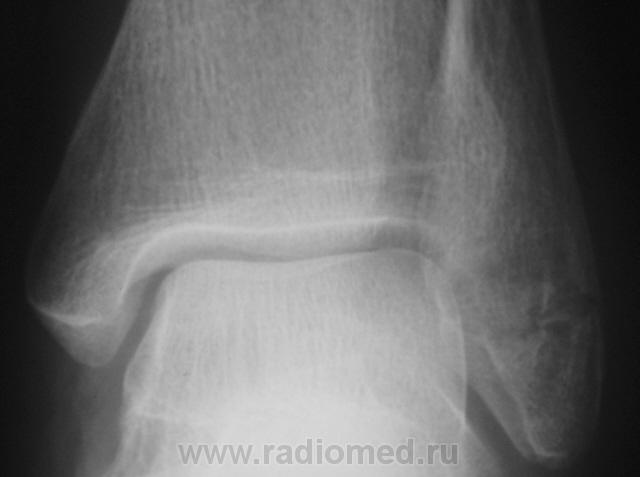

перелом наружной лодыжки без смещения отломков.

Похоже на перелом лодыжки, есть все признаки, но где то подвох, ведь Валентин Львович банальный перелом лодыжки, которые десятки в день проходят, на сайт бы не выставил

Ну, что Вы? Ну какой подвох?